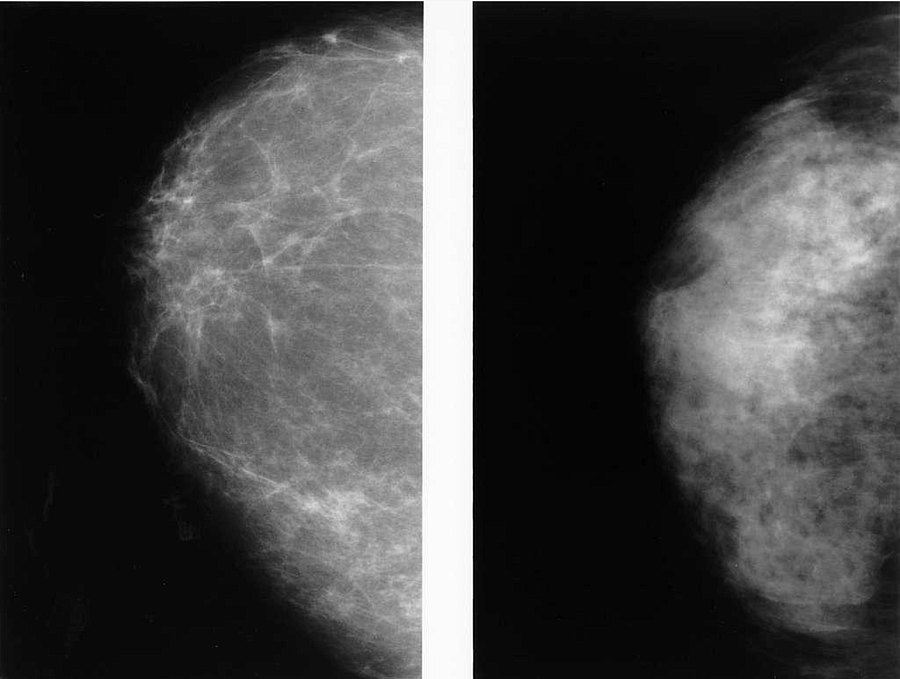

Dense breast tissue affects AAPI women at disproportionately high rates, though it's not clear why, says Dr. Farmah. This matters because both small breast cancers and dense tissue appear white on mammograms — fat looks dark, gray, or black — which makes them harder to detect. So often, says Dr. Farmah, the more subtle breast cancers remain unseen.

A mammography of two breasts. On the left is a dense breast and on the right is a fatty breast.

Abnormal lesions are easier to detect and diagnose in a fatty breast making mammography more accurate.

Dr. Kathy Cho. NIH Radiology // picryl.com